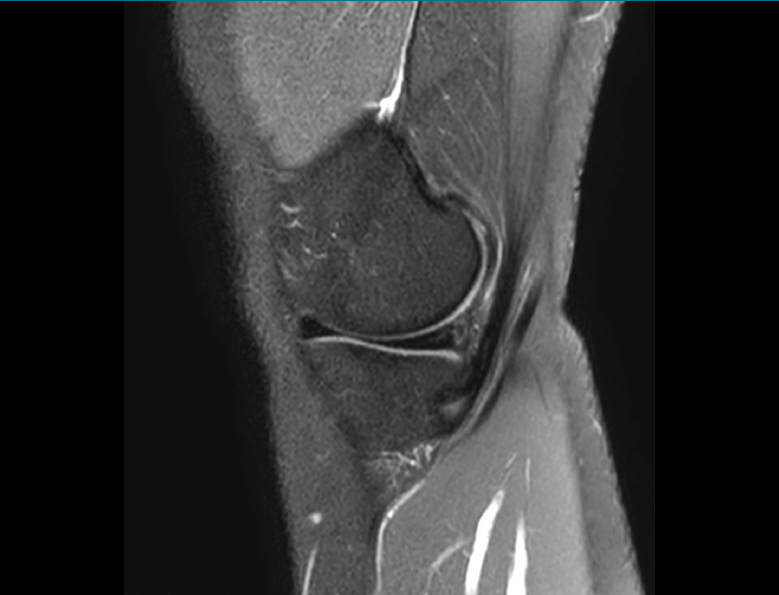

1.2.2. Ligamento cruzado anterior (LCA) (Figuras 40, 41, 42, 43 y 44)

Figura 40. Corte de secuencia sagital T2 Fat-Sat de resonancia magnética de rodilla: ligamento cruzado anterior normal.

Figura 41. Cortes de secuencia sagital T2 Fat-Sat de resonancia magnética de rodilla: rotura central del ligamento cruzado anterior.

Figura 42. Cortes de secuencia sagital T2 Fat-Sat: rotura proximal del ligamento cruzado anterior.

Figura 43. Corte sagital oblicuo T2 de resonancia magnética de rodilla: plastia del ligamento cruzado anterior íntegra.

Figura 44. Corte de secuencia sagital T2 Fat-Sat y T2 de resonancia magnética de rodilla: rotura de plastia del LCA.